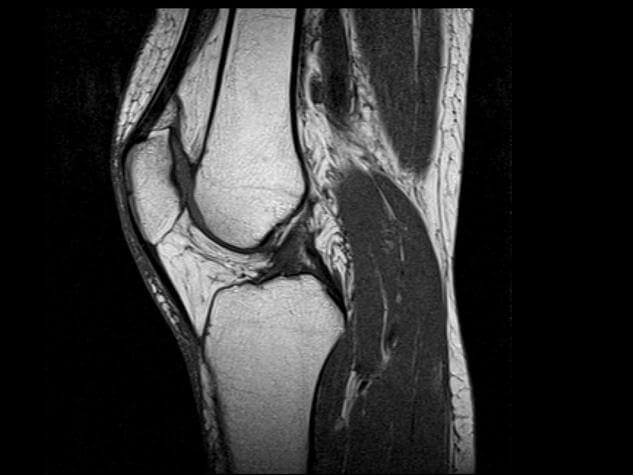

МРТ диагностика основана на действии ядерно-магнитного резонанса. Когда осуществляется магнитно резонансная томография коленного сустава, организм подвергается электромагнитному воздействию, в результате чего меняется положение атомов водорода. Этот эффект фиксируется аппаратом, который преображает полученные импульсы в трехмерное изображение.

Проведение МРТ целесообразно для определения состояния мягких тканей. Такое исследование отчетливо показывает изменения в суставе, что помогает в диагностике болезни или повреждения.

Благодаря проведению МРТ можно увидеть:

- Изменения, произошедшие с костями. На снимках отображаются костные наросты, остеофиты, отломки, опухоли, нарушения целостности. Трехмерное изображение позволяет отследить и величину, и направление повреждений.

- Все патологии, связанные с менисками. Фактически это единственная диагностика, которая детально визуализирует трещины и разрывы, отрывы и микроповреждения хряща.

- Состояние связочных структур. Поэтому для диагностики таких заболеваний как бурсит, синовит, воспаление или разрывов связок, сухожилий лучше делать именно МРТ.